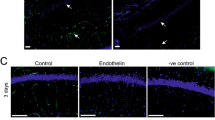

17β-Estradiol prevents axonal damage induced by BCCAO 3 months

(a) Representative photographs of double-immunofluorescent staining for myelin basic protein-2 (MBP2) (green) and NeuN (red, neuron marker) in Sham (Sh) 3 m, BCCAO 3 m, Placebo (Pla) 3 m, and E2-treatment 3 m (scale bars 50 μm, magnification 40×). (b,c,d) Western blot analysis for MBP2 and PHF1 protein expression in the hippocampal CA1 region of various groups at BCCAO 3 m. *P < 0.05 vs. sham group, #P < 0.05 vs. Pla 3 m group, n = 5–6; (e) Ultrastructure of axon, myelin and oligodendrocytes in the hippocampal CA1 region of various groups at BCCAO 3 m. Healthy axon with intact myelin (green star); damaged axon with severe disorganization (yellow star), dense degradation (yellow arrow) and swollen (blue star) myelin sheaths; Healthy oligodendrocytes with intact mitochondria (green star), and damaged oligodendrocytes with dilatation of rough endoplasmic reticulum (blue arrow), swollen mitochondria with broken cristae (red star).